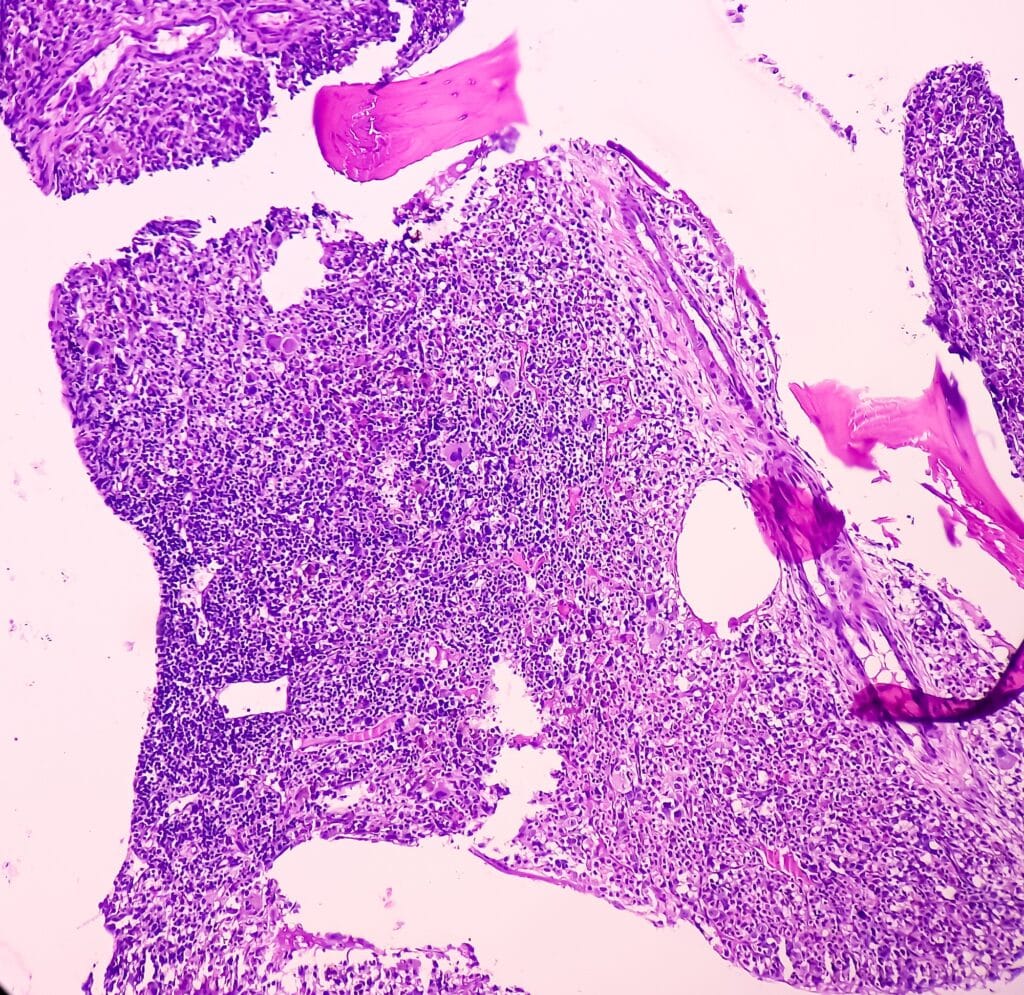

FL originates from germinal or follicular center B-cells and is frequently associated with the chromosomal translocation t(14;18)(q32;q21), which leads to the overexpression of the B-cell lymphoma 2 (BCL2) protein. BCL2 functions as an anti-apoptotic protein, contributing to the survival of malignant B-cells. Additional genetic alterations, such as mutations in BCL-6 and EZH2, have been implicated in FL pathogenesis. These mutations disrupt normal B-cell development and contribute to the malignant transformation of B-cells within the germinal center.